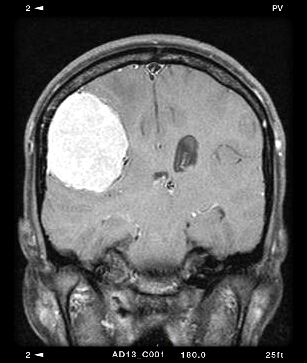

Μηνιγγίωμα κυρτότητας.